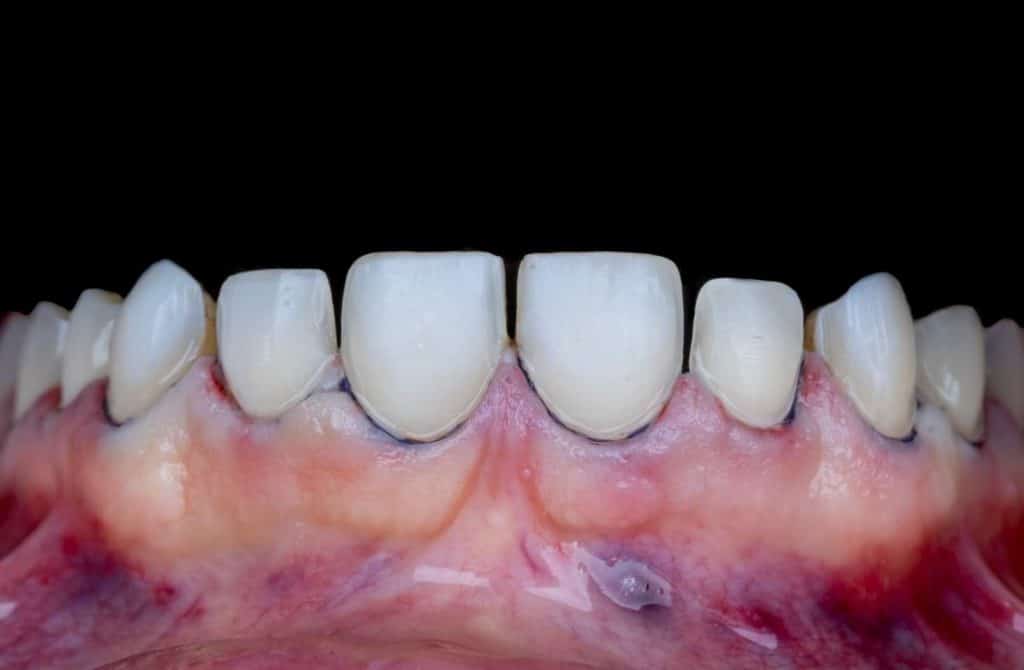

The case presented in this case report is for a 27-years-old female patient with a chief complaint of aesthetic correction for her smile. The patient was unhappy with her smile. After clinical examination, there were previous old composite veneering done poorly and incorrectly to close the multiple interdental spacing. After discussing the various treatment options (i.e., orthodontic treatment, direct, or indirect veneers), indirect ceramic veneering was selected. The step-by-step treatment protocol is presented in the images below.